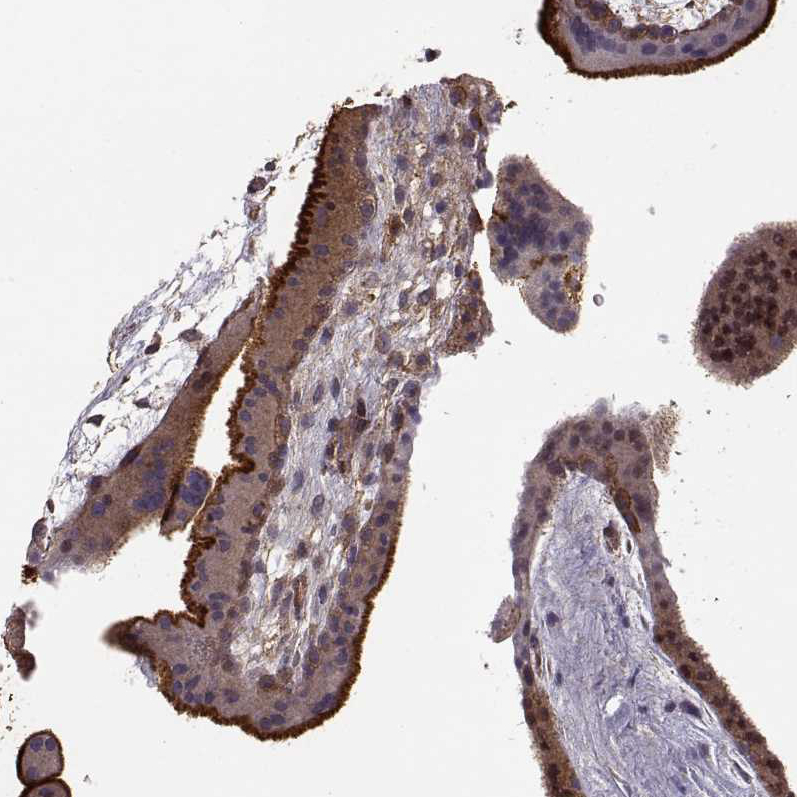

Immunohistochemistry analysis in human small intestine and skeletal muscle tissues using AMAb90976 antibody. Corresponding EZR RNA-seq data are presented for the same tissues.